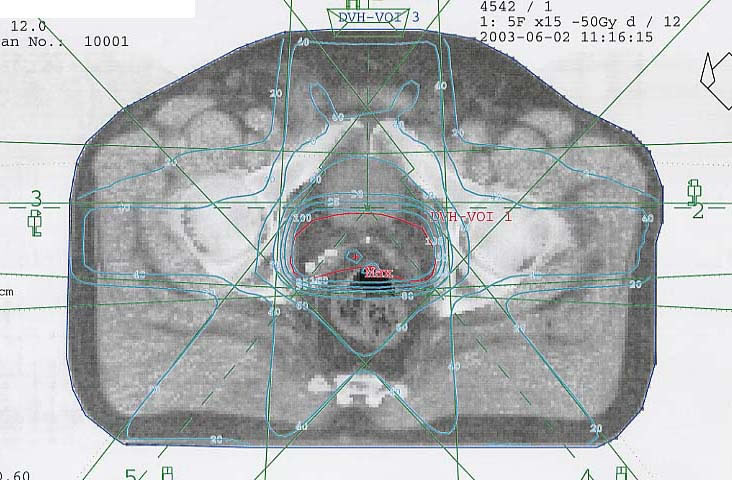

Prostatakarzinom: Bestrahlungsplan

Bestrahlungspläne